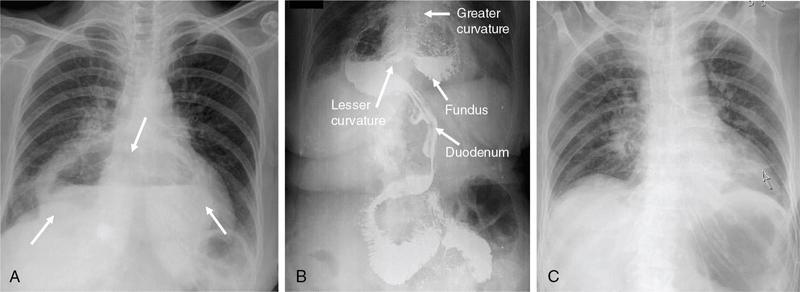

Swarup Nellore, Soumil Vyas, Ujwal Bhure, Ankit Jain, Richa Kothari, Daksh Mehta, Divya Kantesaria, Disha Lokhandwala, Karthik Ganesan The stomach is the most dilated portion of the gastrointestinal tract positioned between the oesophagus and the small intestine occupying the epigastrium, left hypochondrium and umbilical regions of the abdomen performing a multitude of functions including storage and mixing of food and controlling the passage of food into the intestine. Anatomically, the stomach is divided into the following parts (Fig. 8.2.1): the gastric cardia is the portion immediately adjoining the oesophageal opening into the stomach. The fundus is the dome-shaped part above the horizontal plane of the cardiac orifice which undergoes receptive relaxation and is the site of the autonomic pacemaker. The body is the largest part of the stomach extending from the cardiac orifice to the level of incisura angularis (notch like bend in the mid lesser curvature) containing majority of parietal cells (which secrete hydrochloric acid), chief cells (pepsinogen) and enterochromaffin-like cells (ECL). The pylorus is the tubular distal portion of the stomach which is further divided into the gastric antrum and pyloric canal. The pyloric antrum containing G-cells producing gastrin extends from the incisura angularis up to the pyloric sphincter which is an anatomical sphincter formed by concentric thickening of the circular muscle coat and encircles the narrow-slit like pyloric canal. The left dome of diaphragm and oesophagus lie superior to the stomach while the greater omentum and pancreas lie inferiorly. Spleen and liver lie on either side laterally while the transverse mesocolon is located inferolaterally. Diaphragm, greater omentum, left lobe of liver and anterior abdominal wall are anteriorly related to the stomach and contents of lesser sac including pancreas, spleen, splenic artery, transverse mesocolon, left kidney and adrenal gland lie posteriorly. The stomach is embryologically derived from the primitive foregut and is suspended anteriorly by the ventral mesogastrium and posteriorly by the dorsal mesogastrium. During development as the stomach rotates, the peritoneum grows and condenses to form perigastric ligaments, which contain blood vessels, lymphatics, lymph nodes, nerves and fat. The liver forms in the ventral mesogastrium, which develops into the falciform ligament, gastrohepatic ligament (GHL) and hepatoduodenal ligament (HDL). The spleen and pancreas form within the dorsal mesogastrium, which fuses with the posterior abdominal wall to form the gastrocolic ligament (GCL), gastrosplenic ligament (GSL) and splenorenal ligament (SRL). The perigastric ligaments are identified anatomically by the vessels contained in them (Fig. 8.2.2). The gastric cardia and lesser curvature of the stomach are attached to the inferior surface of liver by the lesser omentum by the gastrohepatic ligament respectively which contains the left and right gastric vessels. The inferior free edge of the gastrohepatic ligament extends inferiorly as the hepatoduodenal ligament between the porta hepatis and proximal duodenum gastrophrenic ligament extends between the stomach and the left hemidiaphragm. The gastrocolic ligament identified by the left and right gastroepiploic vessels, connects the greater curvature of the stomach to the anterior surface of the transverse colon. This ligament extends inferiorly as the greater omentum which is a double-layered peritoneum forming a drape anterior to the bowel loops. The gastrosplenic/lienogastric ligament bridges the posterolateral wall of the fundus and greater curvature along the proximal body of the stomach to the splenic hilum and contains the short gastric vessels. The gastrosplenic ligament is contiguous with the lienorenal ligament and both these structures constitute the lateral boundary of the lesser sac. Macroscopically the stomach shows a thick vascular mucosal lining in the form of longitudinal folds called gastric rugae. Microscopic layers of the stomach include mucosa, submucosa, muscularis externa and serosa. The mucosa includes surface mucus cells with simple columnar epithelium, gastric pits, gastric glands, lamina propria and muscularis mucosa. Submucosa includes connective tissue with submucosal Meissner’s plexus. Muscularis externa comprises three smooth muscle layers (longitudinal, circular and oblique) and Auerbach myenteric plexus. The outermost layer called serosa consists of loose connective tissue and visceral peritoneal lining. The arterial supply of stomach is constituted by the branches of celiac artery predominantly in the form of two anastomotic arcades along the lesser and greater curvature. Left gastric artery, a direct branch of the celiac trunk supplies the upper part of the lesser curvature while the lower part is supplied by the right gastric branch of the common hepatic artery arising at the upper border of pylorus. The left gastroepiploic artery, a branch of splenic artery, supplies the upper part of greater curvature and the inferior portion is supplied by the right gastroepiploic artery which is a branch of the gastroduodenal artery. The fundus additionally receives few small short gastric branches from the splenic artery. The veins follow the arteries in their nomenclature. Left and right gastric vein show direct drainage into the portal vein. The splenic vein derives flow from the short gastric and left gastroepiploic vein whereas the right gastroepiploic vein drains into the superior mesenteric vein. Pylorus can be surgically delineated by the prepyloric vein of Mayo lying on its anterior surface. Intrinsic nerve supply consists of the myenteric plexus of Auerbach and submucosal plexus of Meissner. Extrinsic nerve supply consists of sympathetic and parasympathetic components. Sympathetic nerve supply arises from T5 to T9 spinal cord segments supplying the celiac plexus via the greater splanchnic nerve. The plexuses then travel along the respective branches of celiac artery supplying the stomach. Parasympathetic nerve supply is derived from oesophageal plexus of vagus dividing into two vagal trunks. Right (posterior) vagus gives off the posterior gastric branch also called the criminal nerve of Grassi supplying the cardia and fundus of stomach. Right vagus then gives off a celiac branch and continues along lesser curvature of stomach as the posterior gastric nerve of Latarjet supplying the antrum, body and pylorus. Left (anterior) vagus gives off a hepatic branch then continues along the lesser curvature as the anterior nerve of Latarjet supplying the antrum, body and pylorus. Crow’s feet innervation to antropyloric area are important surgical landmarks preserved during highly selective vagotomy receiving branches from both major nerve trunks (anterior and posterior) at the incisura angularis. Anatomical lymphatic drainage is divided into three areas. Area I is the superior two-thirds of stomach draining via the nodes along left and right gastric vessels into the aortic nodes. Area II includes the right two-thirds of the inferior one-third which drains through the nodes along right gastroepiploic vessels via the subpyloric nodes into aortic nodes. Area III includes left one-third of greater curvature draining via short gastric and splenic nodes into suprapancreatic nodes and ultimately into aortic nodes. Gastric lymph node stations are divided into 4 levels with 16 lymph node stations: Paraesophageal nodes below the diaphragmatic hiatus (17) and above the diaphragmatic hiatus (18) are also included. The stomach first appears as a fusiform dilatation in the distal endodermal foregut in the 4th week of embryonic life. The dorsal and ventral mesogastrium suspend the developing stomach to the respective abdominal walls. Preferential growth along the dorsal border of the developing stomach leads to the formation of a convex dorsal border (greater curvature) and a concave ventral border (lesser curvature). The stomach subsequently undergoes a sequence of rotations. The first (90 degrees) clockwise rotation occurs around the longitudinal axis which brings the lesser curvature to the right and greater to the left. This rotation also brings the dorsal mesogastrium towards the left and ventral to the right creating a space behind the stomach called as the lesser sac or omental bursa. The second clockwise rotation occurs around the anteroposterior axis, with the caudal or pyloric part moving upwards and to the right while the cephalic or cardiac portion moves towards the left and slightly downward causing the stomach to assume its final anatomic position. This rotation causes the dorsal mesogastrium to bulge downwards and grow further to eventually become a double-layer apron called the greater omentum. The developing liver divides the ventral mesogastrium into the falciform ligament extending from the ventral abdominal wall to the liver with its lower free edge forming the ligamentum teres, the visceral peritoneum surrounding the liver and the lesser omentum with its two parts – the hepatogastric ligament and hepatoduodenal ligament. The dorsal mesogastrium gives rise to the redundant greater omentum, gastrocolic ligament, gastrosplenic ligament and lienorenal ligament. These perigastric ligaments help us in deciphering patterns of the spread of gastric malignancies and in taking decisions regarding their management and prognostication. These will be further explained in detail under the section of gastric malignancies. An abdominal radiograph is often the initial imaging test for evaluation of acute abdominal pain. The gastric bubble is seen below the left hemidiaphragm in situs solitus. Presence of gastric outlet obstruction may show a distended stomach with gasless small bowel. Hollow visceral perforation is diagnosed by free air seen under domes of diaphragm. Also, the presence and position of various tubes like the nasogastric tube can be confirmed using a radiograph. A fluoroscopic upper gastrointestinal (GI) examination is the radiological study of oesophagus, gastro-oesophageal junction, stomach, duodenum up to duodenojejunal junction by oral administration of contrast. Barium sulphate is a good contrast medium for GI studies as it is radio-opaque, non-absorbable, inert to tissues and can be used for double-contrast studies. Patient should be nil by mouth at least 4 hours prior to the examination. In a single contrast examination, the emphasis is on mucosal relief, luminal distention with contrast material and compression. In the erect position, a small amount of contrast is given to swallow while the oesophagus is visualized under fluoroscopy. The table is then made horizontal and the patient is rotated in a clockwise manner as seen from the foot end of the patient, thus ensuring good coating of the stomach mucosa. Mucosal relief images are then obtained in supine and prone positions to demonstrate the mucosal fold pattern and possible filling defects. After giving some more contrast, the patient is turned oblique with the right side dependent and spot images of the duodenal cap and C loop are taken both in distended and empty states. The patient is again positioned erect and more images of duodenal cap and loop are taken. Further contrast is given to optimally distend the lumen and assess for possible contour abnormalities, wall rigidity and strictures. Compression techniques help assess for filling defects and lesions, in the compressible areas of the stomach. Images are taken in multiple positions – supine, prone, right anterior oblique, right lateral, left posterior oblique in recumbent and right anterior oblique in erect position. Gastric peristalsis and emptying can be observed at fluoroscopy. Advantages of the single contrast technique are that it can be performed quickly, well-tolerated and requires less patient cooperation as compared to double-contrast studies. It can even be performed in physically debilitated patients. Barium is contraindicated in suspected cases of perforation, aspiration, fistula or recent GI biopsy. Single contrast examination can be performed using water-soluble iodinated contrast media in these cases and immediate postoperative patients. Earlier, ionic contrast like Gastrograffin was used. However, due to its high osmolarity, nowadays, non-ionic contrast is preferred as it causes less electrolyte imbalance due to its low osmolarity. Also, it delineates the GI tract very well due to less dilution. Double-contrast studies provide better evaluation of the mucosa than do single-contrast studies. Here, the emphasis is on coating the mucosa with barium and distending the lumen with gas. A well-performed double-contrast study is biphasic and also incorporates some single-contrast techniques. The initial part of the examination is the same as a single contrast examination to obtain the mucosal relief images. Then, gas-forming powder that produces carbon dioxide within the stomach lumen is given with more barium. With the double-contrast technique, the mucosa is coated with a high-density barium suspension and the lumen distended with gas. The patient is rotated in a clockwise manner as seen from the foot end of the patient, thus ensuring good coating of the stomach mucosa. Spot images of the distended stomach are taken followed by the duodenal cap and loop in oblique right-side dependent position. Patient is brought back to erect position erect and more images of stomach, duodenal cap and loop are taken. Further contrast is given to distend the lumen. Residual fluid or food debris in the stomach impairs stomach coating, and lack of adequate coating may preclude visualization of lesions. In addition, optimal gaseous distention is important as underdistention will cause a false appearance of abnormally thickened, and overdistention can obliterate abnormal folds. With normal gastric anatomy, the gastric fundus is best visualized in the upright left-posterior-oblique position, the body in the supine anteroposterior position and the antral-pyloric region in the supine left-posterior-oblique position. The normal gastric mucosal surface should be smooth on double-contrast studies. Areae gastricae appear as reticular networks of polygonal tufts which, owing to the presence of barium in the narrow intervening grooves, are coated with white lines. These are seen most often in the antrum or body of the stomach but can also be seen in the fundus. Areae gastricae are identified on double-contrast studies in 70% of patients and are seen more often in elderly patients. Polygonal tufts should normally range in size from 2 to 3 mm in the antrum and 3 to 5 mm in the body and fundus. Normal gastric folds are more prominent in the proximal to mid stomach and more undulating along the greater curvature as compared with the lesser curvature. Antral folds should be typically effaced with the double-contrast technique. Gastric cardia is characterized by three or four stellate folds radiating from a central point at the gastro-oesophageal junction; this is known as the cardiac rosette and is best visualized in the supine right-lateral position. Ultrasonography (USG) is the modality of choice to visualize hypertrophic pyloric stenosis in infants. Although USG does not play much of a role in adults for imaging of stomach due to reflection of sound waves by air, luminal distension with water may enable to identify mucosal – submucosal pathologies and to assess perigastric relationships in pathologies. CT can not only evaluate the location and anatomy of the stomach, but also provide additional information about the relationship of the stomach to surrounding structures. An optimal CT examination of the stomach includes good stomach distension with a well-visualized wall. Gastric distention can be achieved by the oral administration of negative or positive luminal contrast. Positive contrast agents include a 1%–2% barium suspension or a 2%–3% solution of a water-soluble iodinated contrast agent. Water-soluble agents should be used in cases of suspected perforation. Positive agents provide a bright lumen with better identification of luminal encroachment or diverticula but may limit detailed evaluation of gastric wall enhancement. Positive contrast also may not mix well with gastric contents, producing a pseudotumor appearance. On the other hand, neutral or negative contrasts agents, usually water, produce a low attenuation lumen which allows for more detailed evaluation of the gastric wall and its enhancement pattern following intravenous contrast and is preferred for three-dimensional imaging. Multidetector CT with thin collimation allows for postprocessing in any orthogonal plane. The CT data of the stomach can be manipulated to simulate endoscopic images (virtual gastroscopy). This display technique accentuates the stomach wall and folds. Prior to evaluating the stomach with CT, oral contrast is administered at repeated intervals as well as immediately prior to scanning. Multiphasic scanning after intravenous contrast may be employed at 25–35 seconds (late arterial), 55–75 seconds (venous phase) after contrast injection. Normally, the gastric wall may enhance to approximately 120 Hounsfield Units after intravenous contrast administration. The mucosa may enhance more than the relatively lower-attenuation muscularis propria. Abnormal enhancement of the wall can highlight pathologic processes. The CT appearance of the stomach also depends upon the degree of distention. When well distended, the body and fundus is less than 5 mm thick, though the normal antrum may appear slightly thicker. The presence and pattern of wall enhancement, degree and location of wall thickening, and length of an involved segment may be assessed. Comprehensive MRI examination of the stomach and duodenum by the combined use of T2-weighted single-shot and T1-weighted gradient echo (GRE) – with and without fat suppression, and gadolinium-enhanced 3D GRE helps to detect the spectrum of gastric diseases on MRI. These sequences minimize artefacts from bowel peristalsis, increase the sensitivity of detection of peritoneal and serosal disease by suppressing the high signal of intra-abdominal fat, widen the dynamic range of abdominal tissue signal intensities and distinguish between intraluminal bowel contents and bowel wall. The gastric rugae are well seen on T2-weighted single-shot spin-echo images and their enhancement appears as bands of enhancing tissue arranged perpendicular to the external contour of the gastric wall. The normal gastric wall enhances more intensely than other segments of bowel on immediate postgadolinium SGE images. Water is frequently used as an oral contrast agent when imaging the upper GI segment-stomach and duodenum. Noninvasive dynamic study for assessment of gastric motor function and wall motility can also be done using MRI for diagnosis of gastroparesis. Gastric emptying scintigraphy (GES) is a well-established radionuclide procedure to evaluate patients with suspected gastric motility disorder, more so for non-invasive assessment of gastroparesis in patients with symptoms of postprandial fullness, nausea, vomiting, abdominal pain, bloating, early satiety, loss of appetite, as well as weight loss. Gastroparesis, commonly seen in diabetics, is a condition that affects the normal spontaneous movement of the gastric muscles, leading to impairment of gastric motility, because of which the stomach cannot empty itself of food in a normal fashion and time. GES can also provide useful information with regards to assessment of impaired gastric motility in patients with GERD (gastro-oesophageal reflux disease) unresponsive to routine therapy, diabetics with poor glycemic control, and also in patients with colonic inertia who are being considered for colectomy (since benefits of colectomy are mitigated in patients with concurrent impaired gastric emptying). On the other hand, GES is also useful for assessment of rapid gastric emptying (GE), which is a major factor in dumping syndrome, often seen post peptic ulcer surgery, with or without vagotomy. The solid or liquid component of a meal is radiolabelled with a radiopharmaceutical, which is consumed by the patient and subsequently measured gastric radioactive counts by scintigraphy correlate with the volume of the meal remaining in the stomach. Solid-phase GES is used for the evaluation of gastric motility disorder/gastroparesis. Liquid-phase gastric emptying is generally not clinically useful since it is often in the normal range in spite of deranged emptying for solids even with severe gastroparesis. The preferred radionuclide meal for the gastric emptying scintigraphy includes egg-white radiolabelled with 0.5–1.0 mCi of Technetium-99m (99mTc) [approximate caloric value of 255 kcal]. Two large eggs (egg-whites), two slices of bread, fruit jam, water (120 mL approximately), and the radiopharmaceutical (0.5–1.0 mCi of 99mTc–sulphur colloid). For patients allergic, to eggs, alternative meals like oatmeal or Liquid Ensure nutrient supplement can be used. Reporting should include the percentage of radiotracer retained in the stomach at defined time intervals. The normal reference values for comparison are as follows: Grading the severity of the delay in gastric emptying based on gastric retention at 4 hours of the study: Gastro-oesophageal reflux (GER) is a common condition in infants and children, wherein there is reflux of stomach contents into the oesophagus, due to possible incompetence of gastro-oesophageal sphincter, which can lead to development of symptoms like regurgitation, heartburn, cough and dyspepsia. Children can present with recurrent respiratory infections, iron deficiency anaemia and failure to thrive. It is often a self-limited process in infants and children which usually resolves by 12–18 months of age. On the other hand, gastro-oesophageal reflux disease (GERD) is a chronic pathological process which can be troublesome. Scintigraphic evaluation of gastro-oesophageal reflux, popularly known as ‘milk scan’, is an established imaging modality and has sensitivity of 75%–100%. This radionuclide test for gastro-oesophageal reflux is physiological and quantitative and commonly used for diagnosis in neonates and infants. Four hours fasting is preferred. A liquid meal consisting of formula, milk, or orange juice mixed with the radiopharmaceutical is administered either orally or by nasogastric tube. 99mTc–sulphur colloid. Dose: 0.2 to 1 mCi. After administering the liquid meal and allowing burping, the baby is positioned supine under the gamma camera detector head, including chest and upper abdomen in the field of view. A radioactive marker can be placed at the mouth. Anterior serial dynamic planar images are acquired for around 60 minutes with a framing rate of 5–10 seconds per frame. Delayed anterior static image of the chest may be acquired additionally. The acquired frames are reviewed in cinematic display for visual estimation and to look for reflux of the radiotracer into the oesophagus. Reflux is seen as distinct spikes of radiotracer activity into the oesophagus. For quantitative estimation, the volume of each episode of reflux, frequency of episodes and rate of reflux clearance from the oesophagus are taken into consideration. Percentage of reflux is calculated by drawing an ROI over the oesophageal spike of radiotracer activity and the counts are calculated and expressed as a fraction of the gastric activity counts. Values greater than 5% are suggestive of reflux. Semiquantitative evaluation grades each reflux event: Based on this, four categories can be formulated: The greater the number of high-level reflux events and the longer they last, more severe is the gravity of the problem. Pulmonary aspiration should also be looked for, though the sensitivity of detection is poor. Liquid gastric emptying can be evaluated during the same study up to 2 hours. Normal values for liquid gastric emptying are: Endoscopy is the preferred examination to evaluate for majority of the upper GI symptoms. It is very sensitive in detecting mucosal lesions and simultaneously, biopsies can be taken. In cases of upper GI bleed, endoscopy can not only detect the site and cause of the bleed, but also further treatment like adrenaline/sclerosant injection or ligation can be done. EUS can provide detailed assessment of the 5 layers of the gastric wall and is thought to be the most accurate non-surgical method for local tumour staging (Fig. 8.2.9). For subepithelial (submucosal) gastric lesions, EUS can assess the echogenicity of a lesion, the exact layer of the gastric wall which is involved (accurate T-staging of a tumour) and assess for the presence of blood flow with Doppler ultrasound to help ascertain the likely aetiology. EUS-guided fine needle aspiration may also provide additional diagnostic information. Hiatus hernia is a common positional abnormality of stomach, characterized by herniation of abdominal contents, commonly the gastro-oesophageal junction and stomach, into the mediastinum above the diaphragm through a widened oesophageal hiatus. The oesophageal hiatus is an elliptical opening with complex anatomy formed by the right and left crus of the diaphragm. However, the most common anatomical description is of the right crus splitting into two bundles, the right and left, which form a sling encircling the distal oesophagus and may be reinforced by the left diaphragmatic crus. The distal oesophagus is typically anchored to the oesophageal hiatus by a main restraining structure which is the phrenicoesophageal ligament/membrane (the fascia of Laimer) which is a condensation of endo-thoracic and endo-abdominal fascia and this membrane circumferentially inserts into the oesophageal musculature in close proximity to the squamocolumnar junction (SCJ). The ligament maintains the competence of the oesophageal hiatus and prevents rostral herniation of the gastro-oesophageal junction and stomach. During normal physiological swallowing, the longitudinal layer of the oesophageal muscularis propria contracts with associated oesophageal shortening and stretching of the phrenicoesophageal ligament/membrane resulting in the transient elevation of the oesophagogastric junction and portion of the stomach above the hiatus. At the end of the swallowing mechanism, the elastic recoiling of the phrenicoesophageal ligament/membrane restores the migrated segment to its normal position. With ageing-related wear and tear, the ligament becomes lax with progressive depletion of elastin fibres resulting in proximal migration of the gastro-oesophageal junction and stomach. Other potential risk factors of fibromuscular degeneration are caused by increase in the intra-abdominal pressure as occurs in obesity and pregnancy. The majority of the symptomatic cases of hiatal hernia present with the clinical symptoms of gastro-oesophageal reflux disease (GERD) with most characteristic manifestations of acid regurgitation, heartburn, dysphagia, epigastric or chest pain and even chronic iron deficiency anaemia. Large hernias may also present with early satiety. Conventionally, hiatus hernias are classified into sliding and paraesophageal varieties. The current comprehensive anatomic classification has evolved to include a categorization of hiatal hernias into Types I–IV and is necessary especially regarding the treatment approach, as indications for the surgical method are quite different between sliding and paraesophageal hernias. Majority of hiatus hernias (95%) are sliding hiatus hernias (type I), the remaining type II–IV hernias as a group are referred to as paraesophageal hernias (PEH), with more than 90% of these comprising type III, and the least common being of type II. The assessment of hiatus hernia can be done by various modalities including radiological, manometry and endoscopy studies. The diagnosis of a large hiatus hernia is straightforward, however, identifying a small one is challenging due to mobility of the gastro-oesophageal junction during physiological process like deglutition and respiration. According to the SAGES Guidelines, only those investigations which will alter the clinical management of the patient should be performed. Radiological investigations are usually indicated for diagnosis and presurgical evaluation. Plain chest radiographs demonstrate opacity within the chest typically in the midline overlapping the cardiac shadow or paramedian location (Fig. 8.2.14A), with or without an air-fluid level. Barium swallow radiography is still considered an easy tool for diagnosis of hiatus hernia and provides essential information about the size, location, motility dysfunction, stricture secondary to GERD and stenosis. The evaluation of hiatus hernia requires understanding of anatomical radiographic landmarks like phrenic ampulla, A ring and B ring (or Schatzki’s ring) on a barium study (Fig. 8.2.14B). The phrenic ampulla is a globular structure seen above the diaphragm and below the tubular oesophagus during a contrast swallow. The A ring represents a muscular ring visible at the upper margin of the phrenic ampulla and physiologically corresponds to the highest-pressure zone within the lower oesophageal sphincter, this is often seen as a transient indentation on the oesophageal lumen. The B ring identified in about 15% of individuals, representing the mucosal ring corresponds to the squamocolumnar junction (Z line) and divides the phrenic ampulla into the oesophageal vestibule (A ring to B ring) and the sliding hiatus hernia (B ring to the stomach below the diaphragm). The B ring is a persistent constriction which is not usually not more than 2–3 mm and despite mucosal, can sometimes be symptomatic and require dilatation. By convention, there must be a distance of 2 cm or more between the B ring and the hiatus, to call it a hiatus hernia as physiological migration up to 2 cm is known in normal individuals. Although not reliable, barium studies may also provide information about a short oesophagus, which is identified as a tubular straightened oesophagus with the oesophagogastric junction fixed far above the diaphragm and may be stenotic, the intrathoracic herniated stomach revealing a more elongated funnel/bell – shaped configuration. Cine fluoroscopy provides further additional information about the bolus transit through gastro-oesophageal junction. The major drawbacks of the procedure are non-visualization of B-ring in majority of the cases, radiation exposure, barium/iodine hypersensitivity, contraindication in pregnancy and increase risk of aspiration in paraesophageal hernia causing pneumonitis. Computed tomography (CT) scan is not routinely advised for the primary diagnosis of hiatus hernia but is indicated in cases of suspected complications like volvulus in paraesophageal hernia, obstruction, perforation and strangulation. Multi-slice CT with reconstruction in sagittal, coronal planes and 3D reformations have increased the sensitivity of CT in detection of hiatal hernia. Oesophagogastroduodenoscopy gives added advantage of real-time visual assessment of the mucosa of the oesophagus, stomach and duodenum. The common diagnostic criteria in endoscopic is proximal migration of gastro-oesophageal junction by >2 cm. Endoscopy can also determine the presence of erosive esophagitis or Barrett’s oesophagus. Further, the inability or difficulty of negotiating the scope into duodenum in the presence of a large hiatal hernia is diagnostic of paraesophageal hernia with volvulus. Evaluation of gastric viability is also important in patients undergoing emergency surgery for incarcerated hernias. The disadvantage of the procedure is lack of reproducibility; retching or belching of the patients during examination which can alter the location and anatomy of GEJ and excess air insufflation of the stomach which may exaggerate the size of the hernia. Oesophageal manometry is measured at the level of the diaphragmatic crura, however, manometric landmarks differ from that of barium study and endoscopy, and identified by pressure inversion point. In patients with a paraesophageal hiatal hernia, placement of the manometry catheter across the lower oesophageal sphincter and below the diaphragm can be difficult. The procedure is planned before surgery to exclude motility disorders like achalasia and to verify the integrity of oesophageal peristalsis. pH testing is not essential in the diagnosis of a hiatal hernia, but is necessary for a quantitative analysis of reflux in a case of hernia which can be relieved by antireflux surgery. Confirmation of abnormal gastro-oesophageal reflux on upper endoscopy, or increased oesophageal acid exposure on pH monitoring is necessary prior to operative intervention in patients with a sliding hiatal hernia. Nuclear medicine studies, transoesophageal echocardiogram (TEE) and endoscopic ultrasound (EUS) can also demonstrate hiatal hernias but are not routinely used for diagnosis. The main aim of treatment in symptomatic patient is to reduce the acid reflux. Lifestyle modifications are the first line of management and include weight loss, elevating the head of the bed preferably by 8 inches during sleep, avoidance of meals for atleast 2–3 hours before bedtime and elimination of ‘trigger’ foods. According to the SAGES Guidelines updated in April 2013, the treatment protocols are provided on the basis of types of the hiatus hernia. Type I (sliding) hiatus hernia are usually managed with proton pump inhibitors for 8 weeks, once or twice daily depending on the symptoms. Other alternatives are H2 receptor antagonists and antacids. If the patient is not relieved symptomatically by medication, surgical repair like laparoscopic fundoplication (Nissen or Toupet) can be done. Steps of fundoplication comprise surgically relocating the gastro-oesophageal junction below the diaphragm, maintaining an oesophagogastric angle to prevent gastro-oesophageal reflux, constructing a gastric wrap around the distal oesophagus to support the distal oesophageal sphincter and increase its resting pressure, and finally approximate the diaphragmatic hernia to narrow the widened hiatus. In all symptomatic Type II, III and IV hiatus hernia, surgical repair is strongly recommended as the primary treatment, particularly those with acute obstructive symptoms or which have undergone volvulus. Routine elective repair of completely asymptomatic paraesophageal hernias may not always be indicated and determinants for surgery should include the patient’s age and co-morbidities. These fundoplication surgeries are described later in the text. Gastric volvulus is an uncommon entity and characterized by abnormal rotation of the stomach (usually >180°) along the long or short axis, leading to variable degree of gastric obstruction, which can be of a closed-loop type resulting in strangulation. The exact incidence of gastric volvulus is unclear as patients with a chronic presentation may never be diagnosed.2 Approximately, 10%–20% cases of gastric volvulus occur in children less than 1 year, while the other 80% cases are detected in adults, of which 80%–90% are often encountered in the fifth decade of life.3 No significant predilection is seen with either sex or races. Gastric volvulus can be classified on the basis of aetiology, axis of rotation and duration of onset. While classification based on axis of rotation by Singleton is widely accepted and more relevant to the radiologist, classification based on duration of onset of symptoms is more relevant in clinical assessment. On the basis of axis of rotation (Fig. 8.2.15), gastric volvulus is divided into organoaxial volvulus, mesenteroaxial volvulus and the rarest combined/mixed type. Organo-axial volvulus, by far, the most common type of gastric volvulus, encountered often in the elderly, is characterized by rotation of the stomach along its long axis, that is, cardio-pyloric axis, and resulting in an ‘inverted stomach’ with a horizontal orientation, in the form of anterosuperior displacement of the antrum and posteroinferior rotation of the fundus, so that the greater curvature is displaced superiorly and lesser curvature caudally in the abdomen (Fig. 8.2.16). The site of obstruction in this type of volvulus is at the cardia or at pylorus. It has a higher predisposition towards strangulation and ischaemia. Organo-axial volvulus also shows association with the paraoesophageal hernia or diaphragmatic defects, which allows abnormal movement of the stomach along the long axis. If the degree of rotation is less than 180 degrees, the patient may have an incomplete or partial volvulus which is not completely obstructing and may be asymptomatic; it may be more appropriate to describe it as organo-axial position rather than volvulus. Mesenteroaxial volvulus is less commonly encountered (30%) and accounts for about 29% of cases, is reported more often in young adults or children. It occurs when the stomach rotates around its short (transverse) axis, that is, line connecting the midpoint between the lesser curvature and the greater curvature of the stomach, leading to a vertically oriented stomach, with anterior rotation of the pylorus, antrum and resultant displacement of the antrum above the gastro-oesophageal junction (Figs 8.2.17 and 8.2.18). The site of obstruction is usually at antropyloric region. It is usually not associated with a diaphragmatic defect and is often idiopathic. The third and rarest type of gastric volvulus is the combined type when the stomach shows both rotation along the short and long axes. Based on aetiology of rotation, gastric volvulus can be subdivided into either primary or secondary. Primary gastric volvulus representing 25%–30% of the cases, is more common in the adults. It occurs in the subdiaphragmatic location due to abnormality in the gastric fixation, exclusively because of disruption, laxity or absence of the gastric ligaments which anchor the stomach in place. These ligaments namely the gastrohepatic, gastrocolic, gastrophrenic, gastrosplenic and gastropancreatic ligaments, along with gastro-oesophageal junction and pylorus, provide anchorage and fix the stomach in place intra-abdominally, and prevent abnormal rotation of the mesentery. The primary gastric volvulus usually presents with the mesenteroaxial type of anatomical configuration. Around 70% of patients present with secondary gastric volvulus occurring due to abnormal rotation around the lead point formed by associated disease. The most common association of gastric volvulus is seen with paraoesophageal hiatus hernia. Other causative factors of volvulus include congenital or traumatic diaphragmatic hernia, diaphragmatic paralysis, eventration, connective tissue disorders, previous surgery, adhesions, peptic ulcer, neoplasm, splenomegaly or absence of the spleen and colonic overdistension. On basis of clinical presentation and speed of onset, gastric volvulus can be acute, subacute or chronic. Acute gastric volvulus is a surgical emergency and usually presents with sudden onset epigastric pain, distension, non-bilious vomiting or severe retching, depending on the degree of obstruction. The Borchardt triad of acute volvulus comprises severe epigastric pain and distention, retching but inability to vomit, and difficulty or impossibility of passing a nasogastric tube and may be observed in 70% of cases. Other symptoms include hematemesis due to mucosal sloughing in stomach gangrene or mucosal tear due to retching, dysphagia and dyspnea. Even after prompt treatment, mortality of acute gastric volvulus can be up to 30%–50%, likely secondary to gastric ischaemia, perforation or necrosis resulting from severe gastric obstruction (closed-loop obstruction) causing vascular compromise, making it a life-threatening surgical emergency. Chronic gastric volvulus represents spectrum of diseases from long-standing partially obstructed volvulized stomach with incomplete gastric obstruction on the one side, and intermittent volvulus of stomach with recurrent episode of acute symptoms as the other presentation. Chronic gastric volvulus usually presents with intermittent complaints of vague epigastric pain, non-bilious vomiting, dysphagia or early satiety, dyspepsia and sometimes regurgitation. Due to nonspecific clinical symptoms, diagnosing gastric volvulus is very challenging on the first instance and requires a high clinical suspicion. Diagnostic imaging, along with clinical findings are usually required to achieve the correct diagnosis, and also plays major role in excluding the other common differential diagnosis, like pancreatitis, cholecystitis or pneumonitis etc. The diagnostic modalities useful in suspected cases of gastric volvulus are plain radiographs, upper gastrointestinal contrast (barium) studies, computed tomography and upper gastrointestinal endoscopy. Plain chest and abdominal radiographs may reveal a radiolucent hollow viscus, with or without an air-fluid level, in the chest (when associated with PEH) or upper abdomen. The presence of a nasogastric tube may assist in identifying a malpositioned stomach, and administration of contrast via the nasogastric tube may be confirmatory in this regard. Furthermore, chest radiographs may identify evidence of underlying anatomic abnormalities predisposing to gastric volvulus, including elevated hemidiaphragm due to phrenic nerve palsy or diaphragmatic eventration and rib fractures suggesting prior thoracoabdominal blunt trauma. The plain radiographs may show two air-fluid levels in the antrum and fundus, or a single air bubble with no additional luminal gas in the supine position. A retrocardiac air-fluid level may be seen secondary to hernia and presence of intramural air (gastric emphysema) can be visualized as a radiolucent stripe in the gastric wall. At times a large hiatus hernia may be complicated by volvulus (Fig. 8.2.19). Passage of orally administered contrast like barium can demonstrate the anatomy and also assess the degree of obstruction. As mentioned above, the position of the gastric curvatures and the gastro-oesophageal junction are useful in differentiating the anatomical subtype of volvulus. Computed tomography may be more feasible in an acute emergency setting in order to identify abnormal gastric position, axis and multiplanar reconstructions, especially in the coronal plane, can well elucidate the findings and an associated complication like ischaemia. CT has an overall 90% accuracy in the diagnosis with identification of gastro-oesophageal junction and pylorus lying in close proximity to each other and the transition point at the pylorus known to have 100% sensitivity and specificity. Abnormal antral folds may be seen secondary to the twisting. Stenosis at the neck of the hernia is the CT finding with the second-highest sensitivity (77%–80%) and specificity (94%–97%). CT findings of oedematous or hypoenhancing gastric wall, pneumatosis, pleural effusion or pneumoperitoneum, as indicators of gastric ischaemia are not common but specific when identified. An upper gastrointestinal endoscopy confers both diagnostic and therapeutic benefit, although it may establish the diagnosis in only 28%–45% patients and also, the endoscopic procedure may reduce the volvulus missing the diagnosis by an unwary endoscopist. However, it still remains the best method to detect mucosal ischaemia. Flexible endoscopy also has the advantage of placing a nasogastric tube as it may not be possible with a blind technique at the bedside in the setting of organoaxial volvulus and an obstructed gastro-oesophageal junction. Nasogastric decompression forms the initial management of gastric volvulus with emergent laparotomy or laparoscopy to assess gastric viability, resect gangrenous portion if any and perform de-rotation and gastropexy (fixation of the stomach to the diaphragm and/or the anterior abdominal wall) with or without gastrostomy with repair of secondary factors like paraoesophageal hernia. Erosions are focal shallow areas of ulcerations confined to the epithelium or lamina propria without extending through the muscularis mucosae into the submucosa. NSAIDs are the most common cause of gastric erosions while other incriminated factors include Helicobacter pylori infection, alcohol, viral infections, Crohn’s disease, stress and iatrogenic trauma. Erosions may be visible on double-contrast barium examination obtained with good mucosal coating, as multiple tiny 1- to 2-mm collections of barium, often with a surrounding mound of oedema appearing as a filling defect in the barium pool (Fig. 8.2.20). They are usually located in the gastric antrum and tend to occur along thickened folds.

Double contrast upper GI examination (Figs 8.2.5 and 8.2.6)